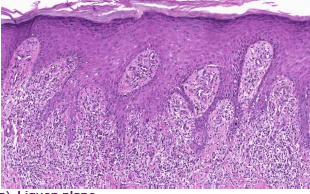

Homem, 39 anos, com relato de lesões placas violáceas nos membros inferiores. Assinale a alternativa que apresenta o diagnóstico que a figura abaixo ilustra.